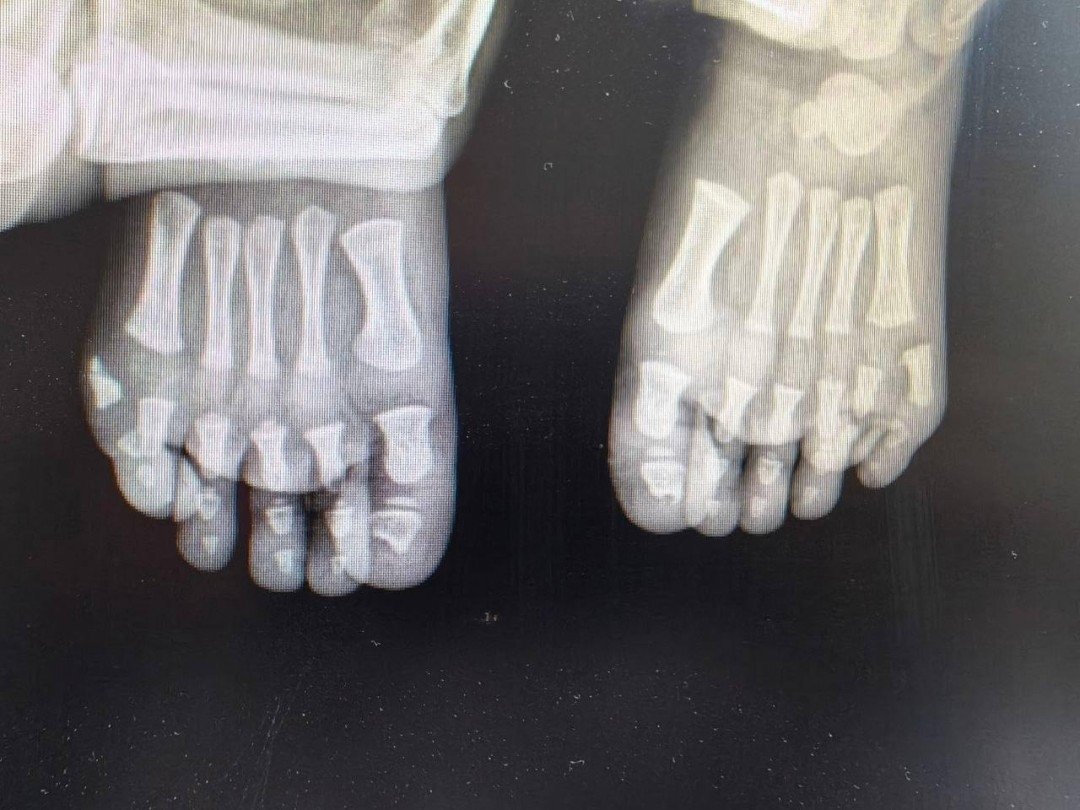

Лишние пальцы мешали ходить мальчику из Подмосковья

Рентгенография пресс-службы Минздрава Московской области

Фото: пресс-службы Минздрава Московской области

StolicaMedia, 14 апреля. В Подмосковье хирурги прооперировали мальчика с лишними пальцами на обеих стопах. Одна операция уже проведена, впереди — второй этап лечения. Об этом сообщили в Минздраве области.

Родители обратились к врачам из-за необычной особенности ребенка — на каждой ноге у него было больше пальцев, чем положено. После обследования специалисты поставили диагноз — врожденная аномалия развития, при которой формируются лишние пальцы. Такое состояние нередко связано с наследственными факторами.

Совместно с семьей было решено провести лечение поэтапно. Сначала врачи выполнили операцию на одной стопе — лишний палец удалили, а структуру восстановили. По словам медиков, вмешательство позволило не только исправить физическую проблему, но и предотвратить возможные психологические трудности в будущем.

После восстановления планируется аналогичная операция на второй ноге. Врачи рассчитывают, что после курса реабилитации ребенок сможет вести обычный активный образ жизни без ограничений.